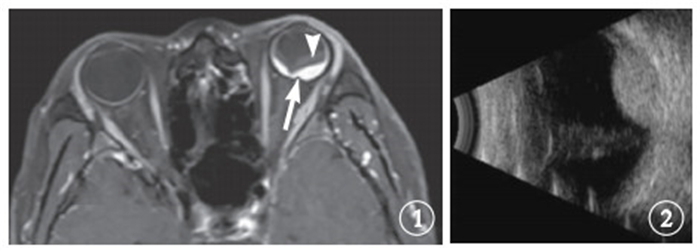

圖1

治療前左眼增強MRI像。可見脈絡膜血管瘤(白箭)及視網膜脫離(白箭頭) ? ?圖 2 治療前左眼B型超聲像。可見脈絡膜血管瘤,腫瘤體積為5.35 cm3

圖1

治療前左眼增強MRI像。可見脈絡膜血管瘤(白箭)及視網膜脫離(白箭頭) ? ?圖 2 治療前左眼B型超聲像。可見脈絡膜血管瘤,腫瘤體積為5.35 cm3

圖1

治療前左眼增強MRI像。可見脈絡膜血管瘤(白箭)及視網膜脫離(白箭頭) ? ?圖 2 治療前左眼B型超聲像。可見脈絡膜血管瘤,腫瘤體積為5.35 cm3

圖1

治療前左眼增強MRI像。可見脈絡膜血管瘤(白箭)及視網膜脫離(白箭頭) ? ?圖 2 治療前左眼B型超聲像。可見脈絡膜血管瘤,腫瘤體積為5.35 cm3